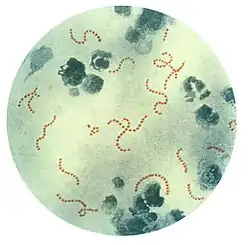

Anaerobic bacteria in the oral cavity include: Actinomyces, Arachnia (Propionibacterium propionicus), Bacteroides, Bifidobacterium, Eubacterium, Fusobacterium, Lactobacillus, Leptotrichia, Peptococcus, Peptostreptococcus, Propionibacterium, Selenomonas, Treponema, and Veillonella.[4] The most commonly found protists are Entamoeba gingivalis and Trichomonas tenax.[5] Genera of fungi that are frequently found in the mouth include Candida, Cladosporium, Aspergillus, Fusarium, Glomus, Alternaria, Penicillium, and Cryptococcus, among others.[6] Bacteria accumulate on both the hard and soft oral tissues in biofilms. Bacterial adhesion is particularly important for oral bacteria.

Anaerobic bacteria in the oral cavity include: Actinomyces, Arachnia, Bacteroides, Bifidobacterium, Eubacterium, Fusobacterium, Lactobacillus, Leptotrichia, Peptococcus, Peptostreptococcus, Propionibacterium, Selenomonas, Treponema, and Veillonella.[4] In addition, there are also a number of fungi found in the oral cavity, including: Candida, Cladosporium, Aspergillus, Fusarium, Glomus, Alternaria, Penicillium, and Cryptococcus.[11] The oral cavity of a new-born baby does not contain bacteria but rapidly becomes colonized with bacteria such as Streptococcus salivarius. With the appearance of the teeth during the first year colonization by Streptococcus mutans and Streptococcus sanguinis occurs as these organisms colonise the dental surface and gingiva. Other strains of streptococci adhere strongly to the gums and cheeks but not to the teeth. The gingival crevice area (supporting structures of the teeth) provides a habitat for a variety of anaerobic species. Bacteroides and spirochetes colonize the mouth around puberty.[7]